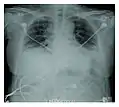

المفتاح الأساسي هو التطور السريع من الأعراض الابتدائية (سعال-حمى-صعوبة تنفس) إلى فشل تام في عملية التنفس. تحت الأشعة السينية تظهر علامة متلازمة الضائقة التنفسية الحادة وأبرزها امتلاء الحويصلات الهوائية بالسائل في كلا الرئتين. أيضاً، عند أخذ خزعة من الرئتين فإنه يظهر على شكل ضرر سنخي منتشر. هناك اختبارات تشخيصية تسهم في استثناء حالات مشابهة، وهذه الاختبارات تتضمن اختبارات الدم وغسل القصبات والأسناخ، ولكن الصورة الإشعاعية والخزعة ضروريان. الصورة الطبية للمرض مشابهة لمتلازمة الضائقة التنفسية الحادة ولكن يختلف هذا المرض في أن سببه غير معروف.